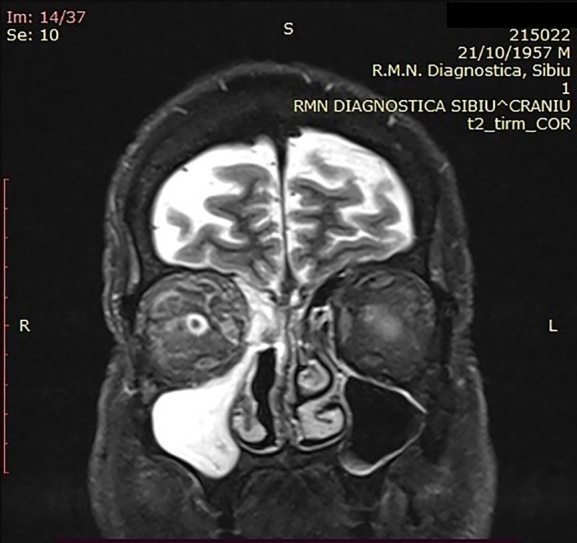

犀牛毒素粘孢子菌病是一种急性侵袭性真菌感染,临床上很少见,多发于严重免疫抑制的患者。然而,在 COVID-19 疾病患者中,粘孢子菌病的发病率急剧上升。本研究旨在讨论 COVID-19 相关粘孢子菌病患者的磁共振成像结果。本研究对 2021 年 2 月 1 日至 2021 年 10 月 30 日期间在三个耳鼻喉科住院和手术的 10 名患者进行了回顾性研究。所有患者均患有鼻腔粘液瘤病,经组织学验证,SARS-CoV-2 RT-PCR 检测呈阳性。所有患者均有鼻窦受累、鼻窦外扩散和鼻窦周围侵犯的记录。磁共振成像与术中发现之间的相关性也得到了评估。黑鼻甲征和鼻甲周围软组织浸润是粘液瘤病的早期磁共振特征。此外,磁共振成像对 COVID-19 相关粘液瘤病的术中发现具有很高的阳性预测价值。

Rhino-sinusal mucormycosis is an acute invasive fungal infection rarely encountered in the clinical setting, occurring in severe immunosuppressed patients. However, in patients suffering from COVID-19 disease a dramatic increase in the incidence of mucormycosis has been recorded. The aim of the study is to discuss the MRI findings of patients with COVID-19 associated mucormycosis. This is a retrospective review of 10 hospitalized and operated patients in three Otolaryngologic Departments between the 1st of February 2021 and the 30th of October 2021. All patients presented nasal mucormycosis, histologically verified along with documented SARS-CoV-2 positive RT-PCR test. The sinus involvement, extra sinus spread and peri-sinus invasion were documented in all patients. The correlation between MRI and intra-operative findings was also assessed. The black turbinate sign and peri-antral soft tissue infiltration are early MRI signs characteristic of mucormycosis. Moreoever, MRI has a significantly high positive predictive value for intra-operative findings in COVID-19 associated mucormycosis.